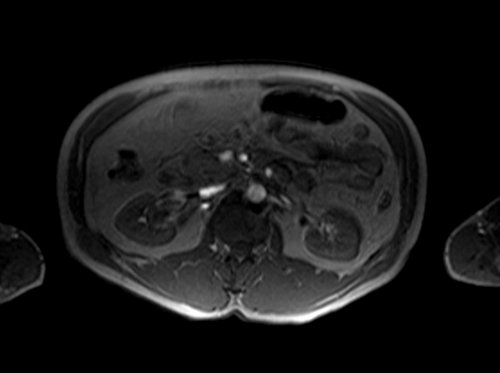

mra abdomen localizer 2 - MRI